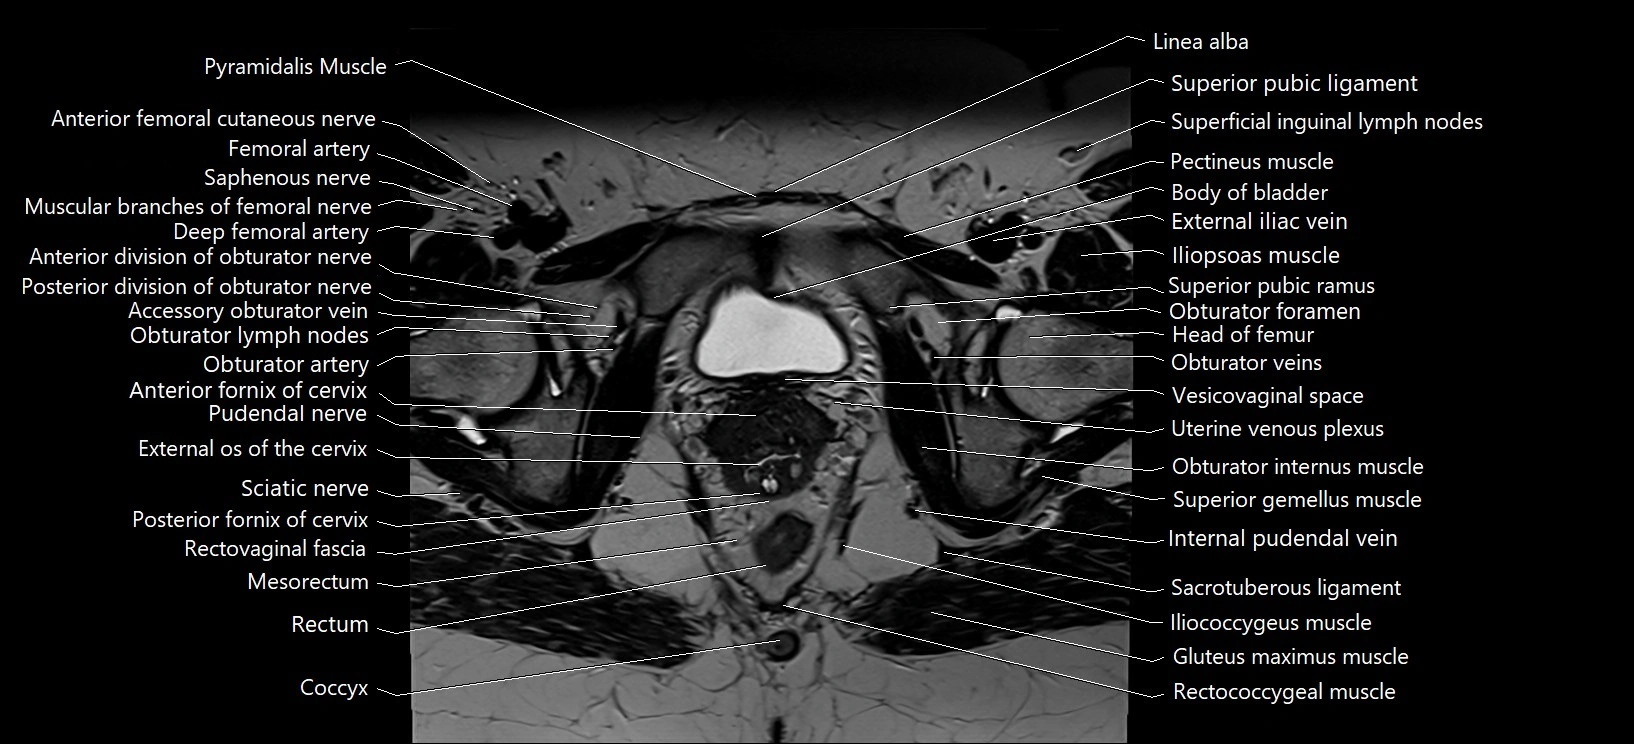

- Anterior fornix of cervix

- Anterior division of obturator nerve (Anterior branch of obturator nerve)

- Posterior division of obturator nerve (Posterior branch of obturator nerve)

- Posterior fornix of cervix

- Pudendal nerve

- Mesorectum

- Rectum

- Coccyx